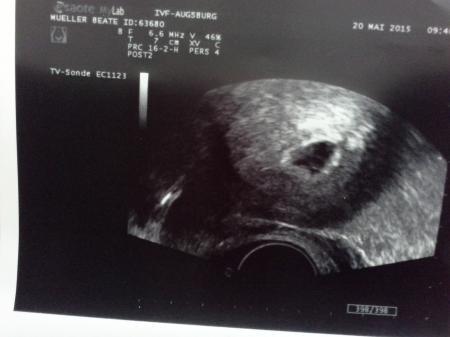

Hallo wurde durch eine IVF schwanger war dann in der ssw 5+5 in der Kinderwunschklinik da sah der Arzt eine fruchthöhle mit Dottersack. Heute bei meiner Frauenärztin ssw 6+4 sah sie nur eine gewachsene fruchthöhle ohne dottersack und embryo warum verstehe ich einfach nicht. Anhang 2 Bilder von der ssw 5+5 wo seht ihr da den dottersack?

Bei mir auf dem Bild siehst du die fruchthöhle und da drinnen ist ein leichter strich der angeblich der dottersack sein soll bin auch kein Arzt leider

Also auf dem unteren bild sehe ich aber sehr eindeutig den dottersack. Das ist das, was aussieht, wie ein kleiner kreis bzw ring (eher rechts unten) und das andere könnte doch der embryo sein! Alles gute!